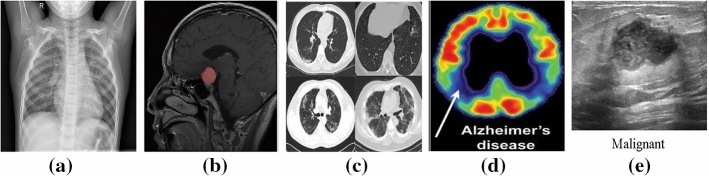

X-ray or Radiography: is the oldest and the most frequently used imaging technique (Ostensen et al. 2001). It is based on the use of wavelength and frequency of electromagnetic radiation which penetrates the skin and is absorbed by the internal tissues at different rates. A 2D representation of the internal structure is provided by monitoring the variance in absorption (Elangovan and Jeyaseelan 2016). There exist two types of radiography: fluoroscopy and projectional radiography. In addition, radiography is considered low cost, quick, easy to perform but harmful to the human body due to the emitting radiations (Ostensen et al. 2001). An example of an X-ray image of a normal chest from the Chest X-Ray Images dataset (Kermany et al. 2018) is provided in Fig. 6a.

Magnetic Resonance Imaging (MRI): is employed to visualize detailed internal structures of the body using magnetic radiation (Ostensen et al. 2001). MRI provides a powerful technique that enables multi-planar three-dimensional views of body organs. As we know, the human body is composed of water molecules. When applying a magnetic field, the relaxation of the hydrogen nucleus of the water molecules is exploited and excited (Elangovan and Jeyaseelan 2016). This operation produces a detectable signal that is used to create images, where diverse rates of relaxation of the different tissues allow the identification of potential abnormalities. Unlike CT, MRI does not utilize ionizing harmful radiations, although it is not recommended as a first-stage diagnosis, especially when the patient owns surgical implants (Ostensen et al. 2001). Example of an MRI image is provided in Fig. 6b. Some examples of related works for MIC from MRI images are (Han et al. 2018, 2021).

Computer Tomography (CT): is a new form of X-ray imaging, where a digital reconstruction of images is employed (Elangovan and Jeyaseelan 2016). An X-ray beam is produced by the X-ray tube and goes through the patient body. Then, the detector captures the beam and reconstructs the 2D or 3D images. Each volume of the image is displayed as a pixel encoding the density or attenuation (Ostensen et al. 2001). In addition, contrast media could be employed to distinguish between structures of similar density. Though CT provides detailed images of internal organs, tissues, bones, and blood vessels. It applies high doses of radiation which can be of potential risk to the patient (Ostensen et al. 2001). Samples of CT scans from the COVID-19 dataset (Zhao et al. 2020) are provided in Fig. 6c.

Positron Emission Tomography (PET): employs a special dye that contains radioactive tracers which are injected into the vein of the examined part of the body. These tracers are then absorbed by certain organs or tissues and tracked by the PET scanner. The latter collects these tracers in areas of higher chemical activity, which promotes the detection of some diseases. Example of a PET image is provided in Fig. 6d from the TADPOLE challenge PET data (Marinescu et al. 2018).

Ultrasound: is a diagnostic imaging technique that uses high-frequency sound waves to examine the internal body structures (Ostensen et al. 2001). Waves whose frequencies are higher than the audio frequency (ultrasound) are sent via conducting gel into tissues with the help of probes. When the waves hit a different structure, they bounce back making it possible to create images (Elangovan and Jeyaseelan 2016). Another type of commonly used ultrasound imaging is Doppler ultrasound which can be used for vascular studies. Ultrasound is cheap and easy to perform, and safe from ionizing radiations (Ostensen et al. 2001). Sample from the Ultrasound breast images dataset (Al-Dhabyani et al. 2020) is provided in Fig. 6e. Some examples of related works for MIC from ultrasound images are Zeng et al. (2020b), Alsharid et al. (2019) and Zeng et al. (2018).

Fig. 6.

Samples of a a normal chest from the Chest X-Ray Images dataset (Kermany et al. 2018), b a brain with meningioma MRI Image, retrieved from the Brain MRI Images for Brain Tumor dataset (Cheng 2017), c CT scans for COVID-19 patients from the COVID-CT-Dataset (Zhao et al. 2020), d PET scans from TADPOLE challenge PET data (Marinescu et al. 2018) for an Alzheimer’s disease and e an image from the Ultrasound breast images dataset (Al-Dhabyani et al. 2020)